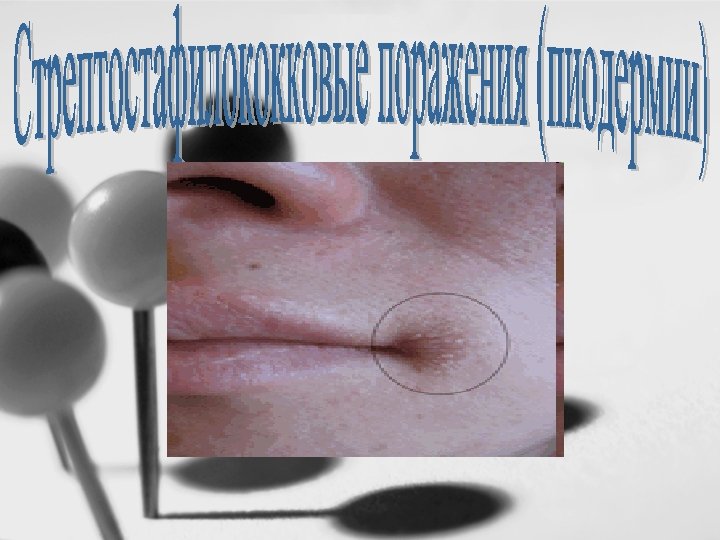

Этиология • За последние годы частота этого заболевания значительно возросла. Пиодермии часто осложняют острый герпетический стоматит, многоформную экссудативную эритему, хронический экзематозный хейлит. Стрептостафилокковые поражения наблюдаются также при повреждении слизистой оболочки полости рта, губ (трещины), кожи околоротовой области у детей с пониженной сопротивляемостью к гноеродной инфекции, ослабленных, получающих несбалансированное питание.

Проявления стрептококкового пиодермии : фликтены с воспалительным венчиком на коже подбородка, носа и щек, ссыхающиеся в тонкие желтоватые корки.

Проявления стрептостафилококкового пиодермии: фликтены вокруг рта и носа, ссыхающиеся в толстые желтые слоистые корки